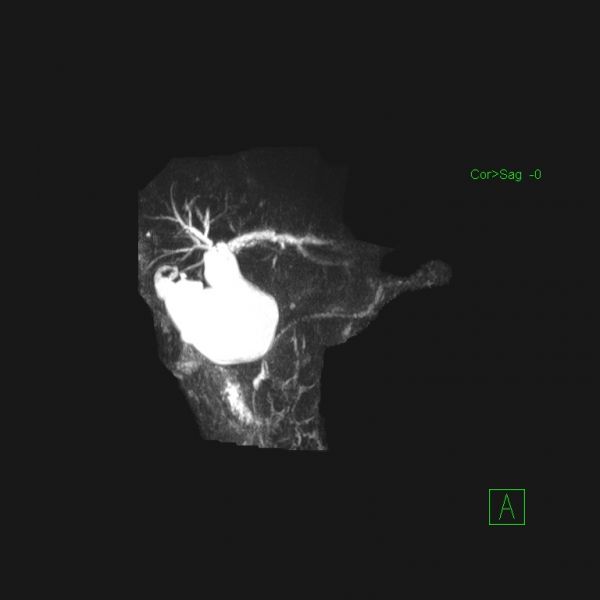

石某某,因突发上腹痛疼痛10小时入院。入院时完善急诊血常规、生化、肝功能、胰代谢以及肝胆脾增强CT等检查,考虑诊断“急性胰腺炎;胰腺假性囊肿”,进一步完善磁共振平扫+MRCP检查,确诊为胆总管囊状扩张症(Ia、C-P型)并发急性胰腺炎。首先进行胰腺炎治疗,予以禁食禁饮、抗炎、护胃、补液、抑制胰腺内外分泌、通便等治疗。经积极治疗,病情稳定后,复查生化相关指标恢复正常,王文儿主任指示:完善术前相关评估,有限期手术指征,无明显手术禁忌,于4月16日在麻醉科及护理工作人员的积极配合下成功完成全腹腔镜下胆总管囊肿剥除+胆囊切除+胆肠内引流术,术中于胆肠吻合口后方放置一18#引流管,术中生命体征平稳,术中失血量约50ml,手术历时约4.5小时,麻醉复苏成功后安返病房。

在诊疗过程中科学的诊疗决策对于患者诊治过程中的顺利推进起到举足轻重的作用。患者因上腹痛10小时入院,完善相关生化以及CT影像检查发现:第一,胰代谢异常明显,结合临床表现和影像学检查,急性胰腺炎诊断明确;第二,上腹部CT发现胰头区有囊性占位,报告:假性囊肿形成可能。王文儿主任仔细阅片以及根据发病特点分析,胰头区囊性占位极似胰腺假性囊肿,根据腹痛特点及胰代谢指标分析,最容易考虑诊断为“急性胰腺炎并假性囊肿形成”。但是,王文儿主任进一步指出:发病时间短,一般不可能在短时间内形成假性囊肿,那么就应该考虑是否还有其他病变?是否考虑胆总管囊状扩张症?那么,就需要进一步完善检查,诊断胆总管囊状扩张症最有价值的方法就是MRCP,于是完善MRCP检查后证实了王文儿主任的推断,最终患者诊断为胆总管囊状扩张症(C-P型)并急性胰腺炎。最后我们的诊疗方案分两步走:第一,积极治疗并发症。第二,待病情稳定后实施腹腔镜胆总管囊肿剥除+胆囊切除+胆肠内引流,以加速康复理念为指导,实现患者快速康复出院,赢得病人的信任。

术前影像图片